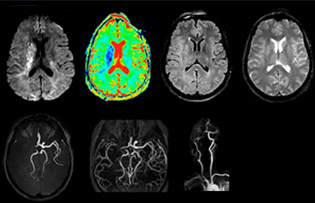

“The biggest challenges are properly characterizing the lesion and giving the surgeon all the information needed, such as the location of vessels and functional areas. Sometimes a very comprehensive exam is necessary, such as when a mass has been discovered at another hospital after which the patient is referred to us. We then do both lesion characterization and preoperative imaging in one exam, so both morphologic and functional assessment. For morphologic assessment we will use pre- and post-contrast T1-weighted imaging, FLAIR to assess infiltration, and diffusion. For functional characterization we will perform perfusion, spectroscopy, and susceptibility weighted imaging to look for micro vessels or micro hemorrhage inside the lesion[4]. For preoperative imaging we perform specific morphologic imaging that is compatible with the navigation system; depending on the location of the tumor, we would do fMRI or DTI.”

“In France, every stroke is usually imaged with MRI, not CT, even for emergency treatment.” “In France, stroke is usually imaged with MRI, not CT, even for emergency treatment. This is because MRI helps us directly visualize ischemia in the acute phase, but can also help rule out differentials such as MS and hematoma. In addition, we can assess the intracranial and extracranial vessels during the same examination,” says Dr. Savatovsky.

The first challenge in MRI of stroke is speed. The patient typically arrives from an ambulance in the MRI preparation room and the installation is done on a separate dock outside the scanner room. “The venous access is placed during the neurological examination. If the delay from the first symptoms allows the patient to receive thrombolysis we do a very fast examination that typically lasts about 11 minutes including the pre-scans. In the case of transient ischemic stroke we usually add ASL perfusion because in some symptoms with negative diffusion, ASL sometimes indicates a vascular origin.”

“Ingenia provides great flexibility in the parameters setting. We can tune a sequence the way we want,” says Dr. Savatovsky. “For example, in a stroke exam we use a FLAIR sequence of about two minutes instead of the four-minute FLAIR we use for MS. The diffusion is 30 seconds, the T2*-weighted scan is 30 seconds, the angiography scan time is less than one minute. Ingenia is a great scanner in that situation; even with these fast sequences we can achieve good images with good SNR. When the first sequence tells us that it’s not an ischemic stroke but a hemorrhagic stroke, we may switch to a time-resolved angiography to look for vascular malformations and venous thrombosis.

“Every center is different, but for me the ideal protocol for stroke includes diffusion weighted imaging, FLAIR, and fast susceptibility imaging,” says Dr. Savatovsky. “Our fast susceptibility weighted imaging takes 50 seconds, so it’s as fast as T2*-weighted imaging. It visualizes hemorrhage but also the clots. We also do 3D MR angiography that provides information on cervical and brain vessels. If the patient does not need immediate treatment, or if additional information is needed to decide on treatment, we might also add perfusion imaging and post-contrast T1-weighted imaging.”